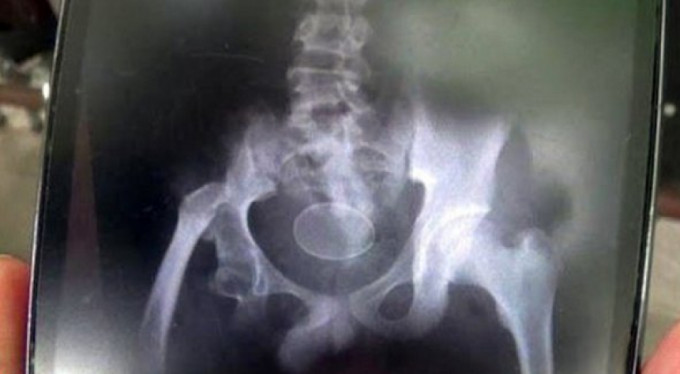

Akmal adlı çocuk, kendisine inanmayan doktorların gözü önünde 2 kez yumurtladı. Daily Star'ın haberine göre; çocuğun rektumuna yumurtaların dışarından sokulmuş olabileceğini ve insan sindirim sisteminde yumurta oluşumunun mümkün olmadığını söyleyen doktorlar, çocuğu Syekh Yusuf Hastanesi'nde karantina altında takip etme kararı aldı.